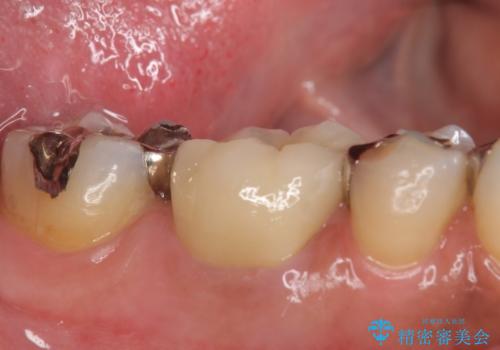

- 右下奥歯の歯茎がよく腫れるので診て欲しいといらっしゃった方の症例です。

診査の結果、右下6番目の根尖病変を認めたため再根管治療を行いました。

また右下7も根管充填が不十分なため再根管治療を行いました。

症状の消失を確認後、オールセラミッククラウンによる補綴を行いました。